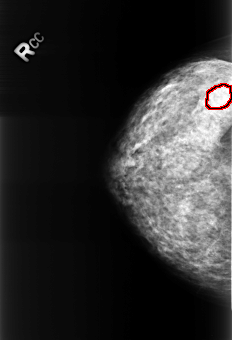

B_3251_1.RIGHT_CC

FILE: B_3251_1.RIGHT_CC.OVERLAY

TOTAL_ABNORMALITIES 1

ABNORMALITY 1

LESION_TYPE CALCIFICATION TYPE PUNCTATE DISTRIBUTION REGIONAL

ASSESSMENT 2

SUBTLETY 5

PATHOLOGY BENIGN_WITHOUT_CALLBACK

TOTAL_OUTLINES 1

BOUNDARY